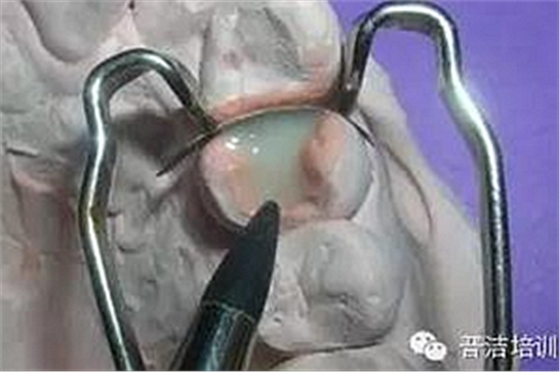

十一、分開粘結(jié),用聚四氟乙烯保護(hù)修復(fù)好的牙齒

十二、洞內(nèi)置入粘結(jié)水門汀,將高嵌體就位

十三、用器械使修復(fù)體完全就位

十四、完全就位前去除多余的水門汀,并用牙線和探針仔細(xì)去除牙齒之間的多余材料。

十五、修正、拋光